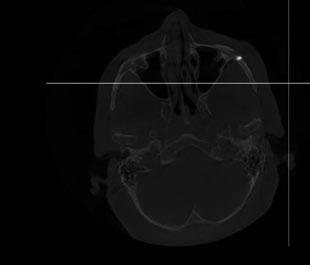

Por otro lado, es imprescindible y fundamental realizar un CBCT de la arcada a tratar para poder visualizar los tejidos duros y hacer una primera valoración del lecho implantario y de la patología existente. (Figura 4)

La planificación comienza con un CBCT para evaluar la densidad ósea del cuerpo cigomático, región pterigoidea y pared lateral de la cavidad nasal. Se realiza incisión crestal o vestibular extendida con colgajo mucoperióstico para exponer el reborde residual. Los implantes

cigomáticos se colocan con angulación hacia el cuerpo del cigoma desde el sector premolar, con perforación bicortical. Es esencial el estudio imagenológico con CBCT y escaneado intraoral para confeccionar una guía quirúrgica específica. En este caso se realizó una planificación virtual con software 3D para determinar la trayectoria ideal de los implantes transnasales y cigomáticos, asegurando que los ejes emergentes coincidan con el futuro diseño protésico.